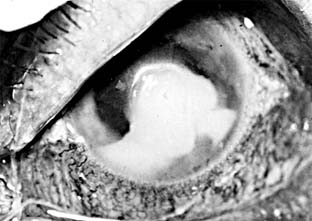

Pneumococcal corneal ulcer usually occurs 24-48 hours after inoculation of an abraded cornea. It typically produces a gray, fairly well circumscribed ulcer that tends to spread erratically from the original site of infection toward the center of the cornea (Figure 6-1). The advancing border shows active ulceration and infiltration as the trailing border begins to heal. (This creeping effect suggested the term "acute serpiginous ulcer.") The superficial corneal layers become involved first and then the deep parenchyma. The cornea surrounding the ulcer is often clear. Hypopyon is common. Scrapings from the leading edge of a pneumococcal corneal ulcer usually contain gram-positive lancet-shaped diplococci. Drugs recommended for use in treatment are listed in Tables 6-2 and 6-3. Concurrent dacryocystitis should also be treated.

Figure 6-1

Figure 6-1: Pneumococcal corneal ulcer with hypopyon.